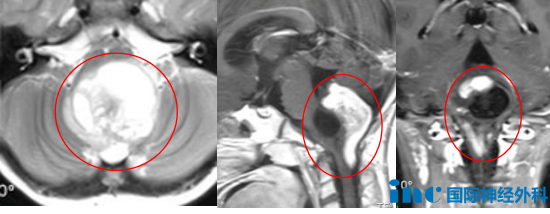

头颅磁共振成像(MRI)发现:第四脑室下方-枕大孔区-上段颈椎椎...